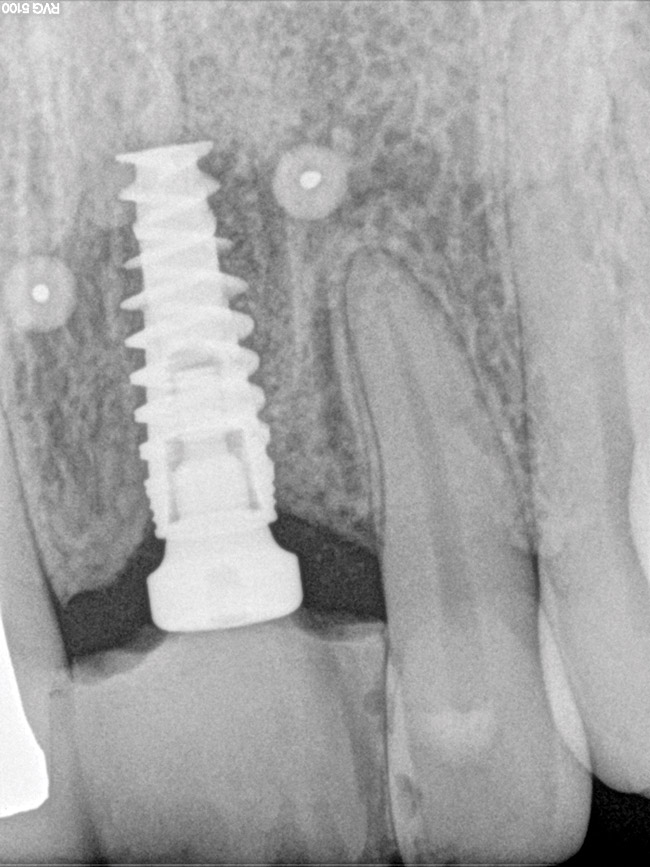

Figure 3  Periapical (PA) radiograph, definitive restoration, of patient in Figure 2.

Figure 3

When three or more implants in a row are planned, concepts of spacing and angulations, parallelism in all dimensions, proximity to anatomic structures, and relationships between implant positions and planned restorations are all significant considerations. CT/CBCT-guided surgery allows for the ideal placement of multiple dental implants according to the planned restoration while taking these issues into consideration (Figure 2 and Figure 3). Implants can be placed flaplessly and immediately loaded.6-8,11-14,25-29